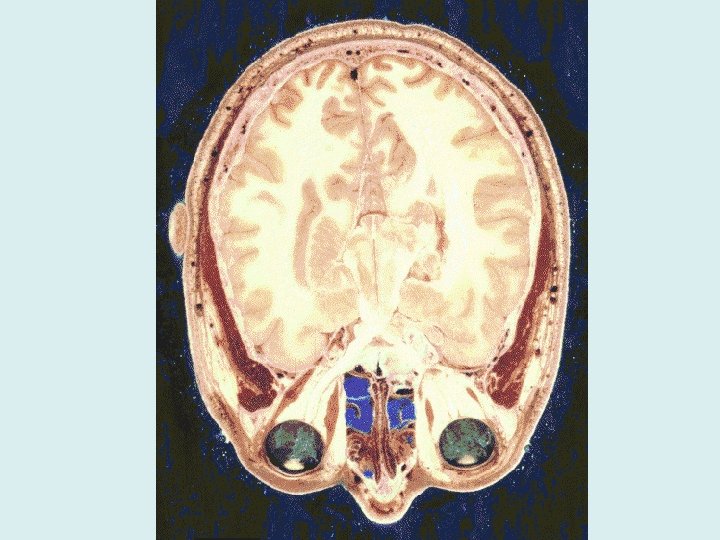

Meninges of the CNS • Dura Mater: thick, outermost • Arachnoid: spiderweb-like • Pia Mater: innermost, clings to brain

Cerebrospinal Fluid • A watery broth that circulates and protects the brain & spinal cord from trauma • Formed by choroid plexuses, circulated by ependymal cells • A very weak salt solution with low amounts of protein (200 m. L total; 135 -150 m. L around the brain) • Any change in composition (levels of protein, presence of blood, glucose levels) may be a sign of meningitis, tumors, infection, or something else • Tested through a spinal tap

• Ventricles – Set of structures (openings) containing CSF in the brain – Drains into the central canal of the spinal cord